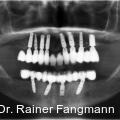

Die Daten der DMS V zeigen, dass in der Patientenaltersgruppe der 65- bis 74-Jährigen im Durchschnitt 12,5 Prozent völlig zahnlos sind. Die zahnlosen Ober- und Unterkiefer stellen eine typische Indikation für herausnehmbaren Zahnersatz dar. Fotos: © Dr. Dr. Rainer Fangmann